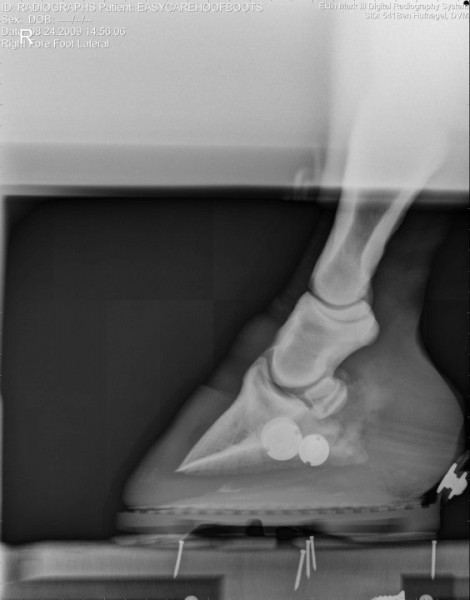

Společnost EasyCare si dělá vlastní průzkumy-výzkumy… zde jsou zajímavé fotografie jak to vypadá když je kopýtko v botě, zůstává ve svém přirozeném tvaru, kopytní mechanismus je neomezený a kůň ho má možnost plně přirozeně využívat 🙂